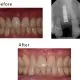

case-studies Case #5 Two front discolored teeth were restored with Cerec crowns. It took 2 hours. They are beautiful and strong.February 24, 2024/by Rich https://sunnyvaledentalspecialty.com/wp-content/uploads/2018/08/Untitled-2.jpg 491 462 Rich https://sunnyvaledentalspecialty.com/wp-content/uploads/2017/03/logo.png Rich2024-02-24 12:32:092024-05-02 11:10:00Case #5